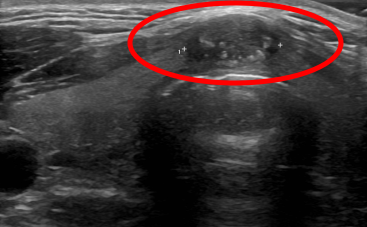

붉은 동그라미 안에 보이는 점선 위에 보이는 반짝반짝한 물체가 바늘이 갑상선 결절을 통과한 모습입니다 바늘을 이용하여 갑상선 결절에서 세포를 흡인하였습니다.